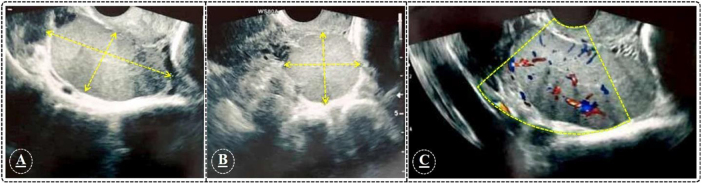

Clinical presentation: A 43-year-old woman with chronic pelvic pain was admitted to hospital. Medical history showed a car accident (at the age of 5 years) and severe spleen trauma followed by splenectomy. Patient assessment and sonography procedure revealed the presence of retrouterine mass with primary endometriosis diagnosis. Exploratory laparotomy was applied and total hysterectomy and bilateral salpingo-oophorectomy were conducted. The mass was excised and histopathologic assessment revealed the splenosis with pseudo-endometriosis symptoms.